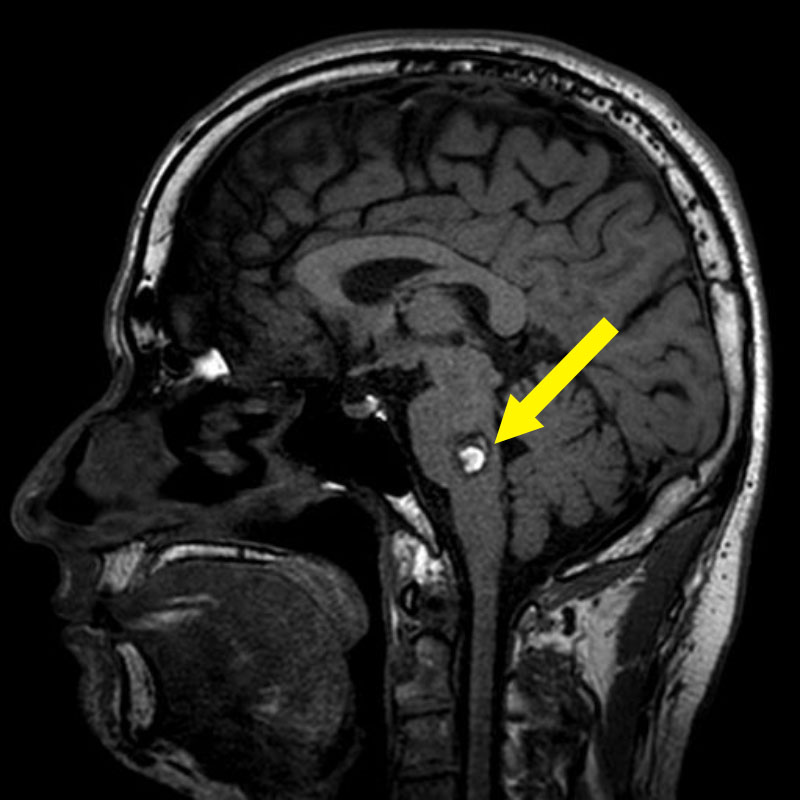

脳幹部

海綿状血管腫

出血の予防目的

熊本県の病院

No.No.62 手術前1

No.No.62 手術前2

No.No.62 手術後1

No.No.62 手術後2

CT/MRにより完全に摘出されたことが確認された